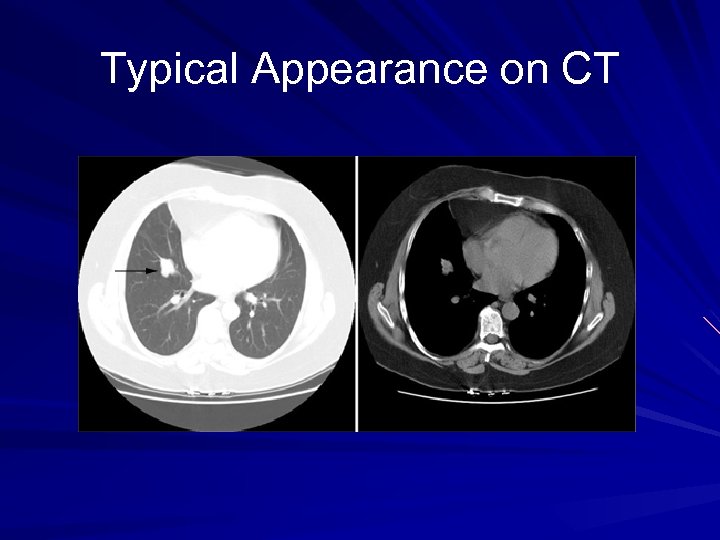

Diagnosis CXR – – 75% have abnormal CXR Round/ovoid mass 2 -5 cm Hilar or perihilar CT chest – 5 -20% have mediastinal or hilar LAD Bronchoscopy – 75% amenable to bx (centrally located) – Intact overlying bronchial epithelium Peripheral lesions: CT-guided bx/aspiration vs operative resection

Typical Appearance on CXR/CT

Typical Appearance on CT